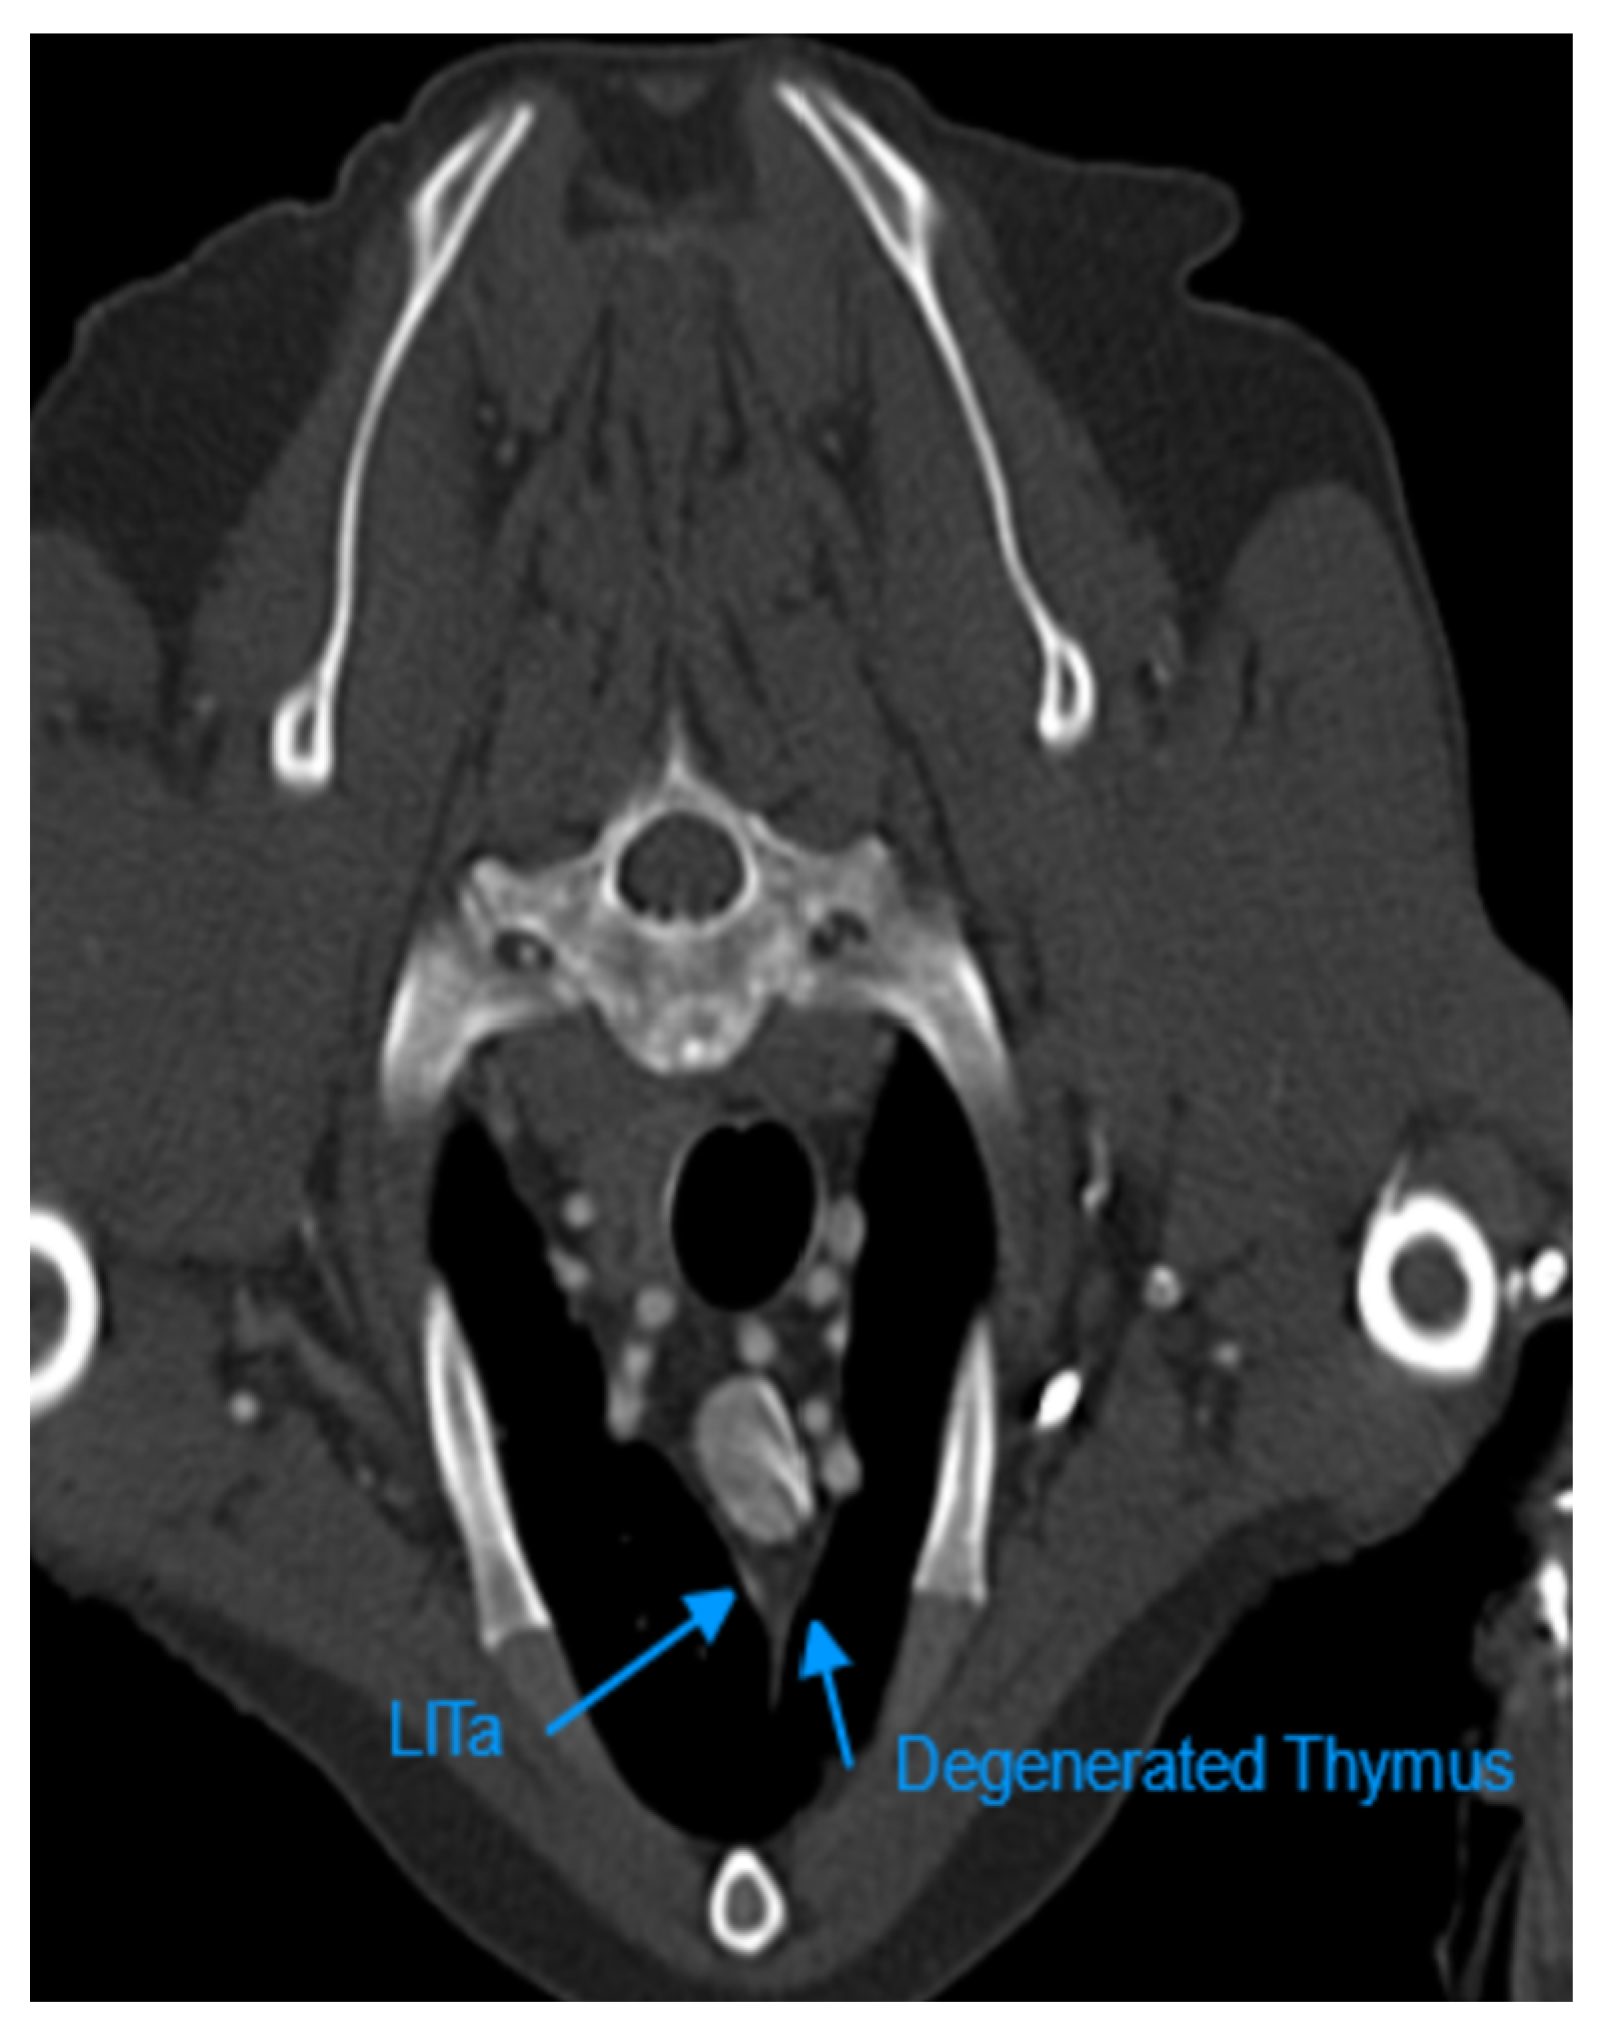

Figure 6. Transverse Section of a Contrast-Enhanced CT scan Examination at the Level of T2 of a 12-year-old Male Terrier Dog. The shorter arrow shows Complete Fatty Degenerated Thymus which is not Distinguishable from Mediastinal fat. LITa: Left Internal Thoracic Artery.